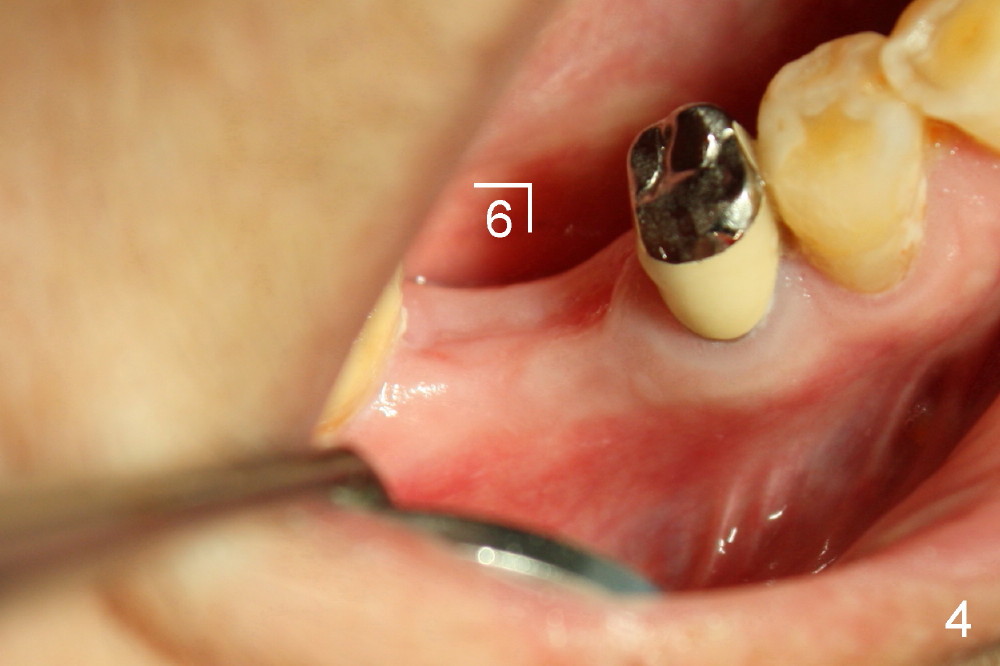

几个月前右下六根尖周炎,根管治疗无效,Amoxicillin引起全身过敏性皮炎,最后拔除。术后六周伤口愈合,牙槽骨有些吸收(图四),通过骨扩张,植入6x17mm植牙(图五,牙槽骨好像不再萎缩了,与图四相比),伤口挺密合,不需要缝线,但是不是天衣无缝,细菌食物还是会进入伤口造成感染。服用抗生素好像不是个好主意(过敏史),灵机一动:使用periodontal dressing盖住植牙(图六)。但是术后病人抱怨局部肿痛,最后还是服用灭滴灵。术后第九天,患者回诊所左上七牙冠粘固,顺便拆除右下periodontal dressing(图六),dressing下面伤口愈合了吗?还是象图二那么糟(婚纱后面新娘漂亮吗)?